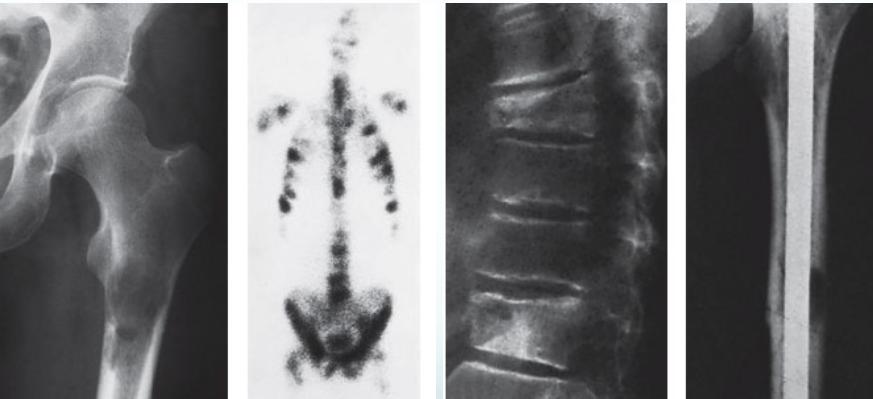

- Osteoblastic in ca prostate

Metastatic - Prostate

Source: Orthopedic Radiology. A Greenspan. Lippincott-Raven